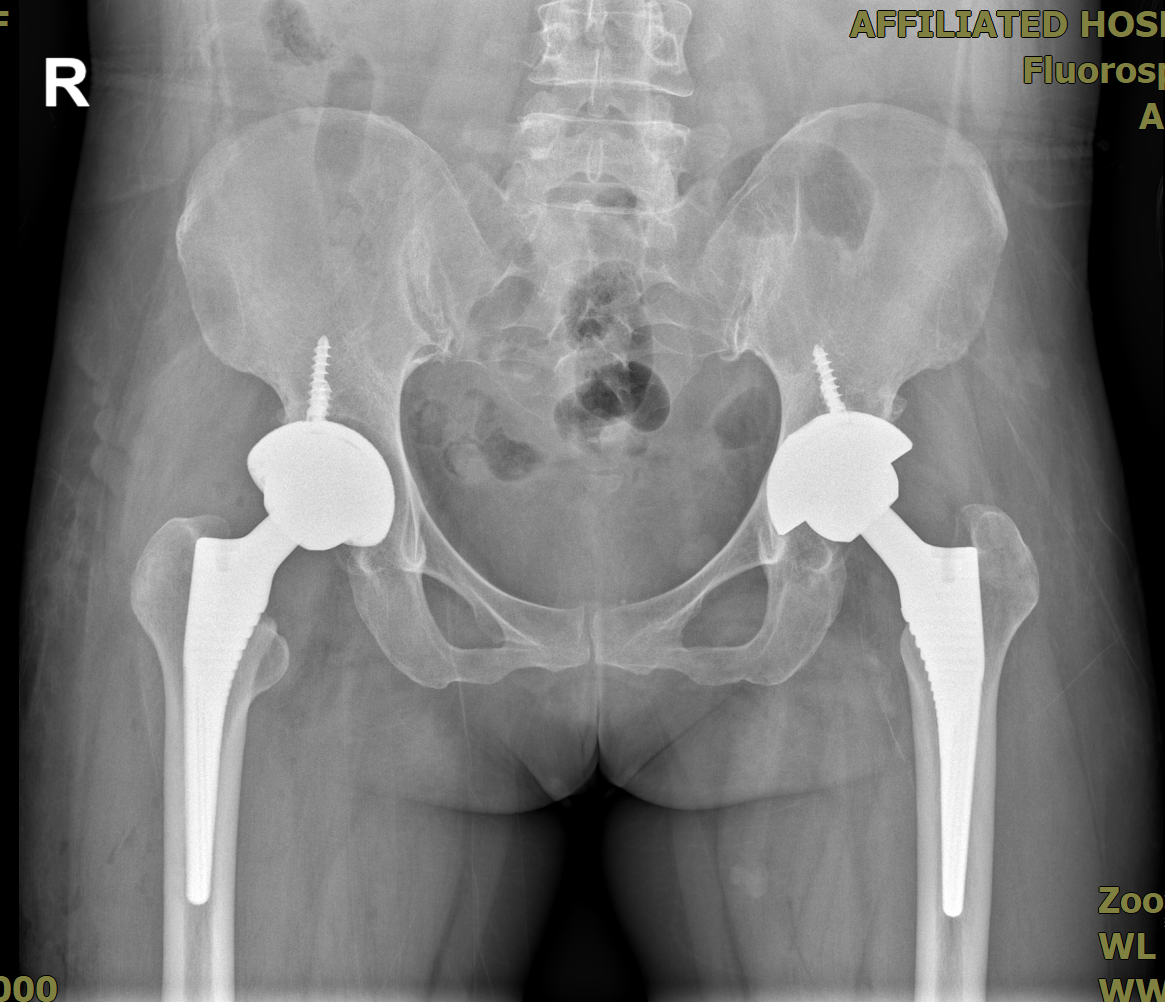

患者*女士,因“右侧股骨头缺血性坏死”入院,伴有左髋关节置换术后史,身体状况复杂。术前影像显示右侧股骨头变扁、关节间隙狭窄、半脱位等严重病变,需行右侧全髋关节置换术。

左髋关节置换术后

右人工全髋关节置换及右侧骨缺损重建术后